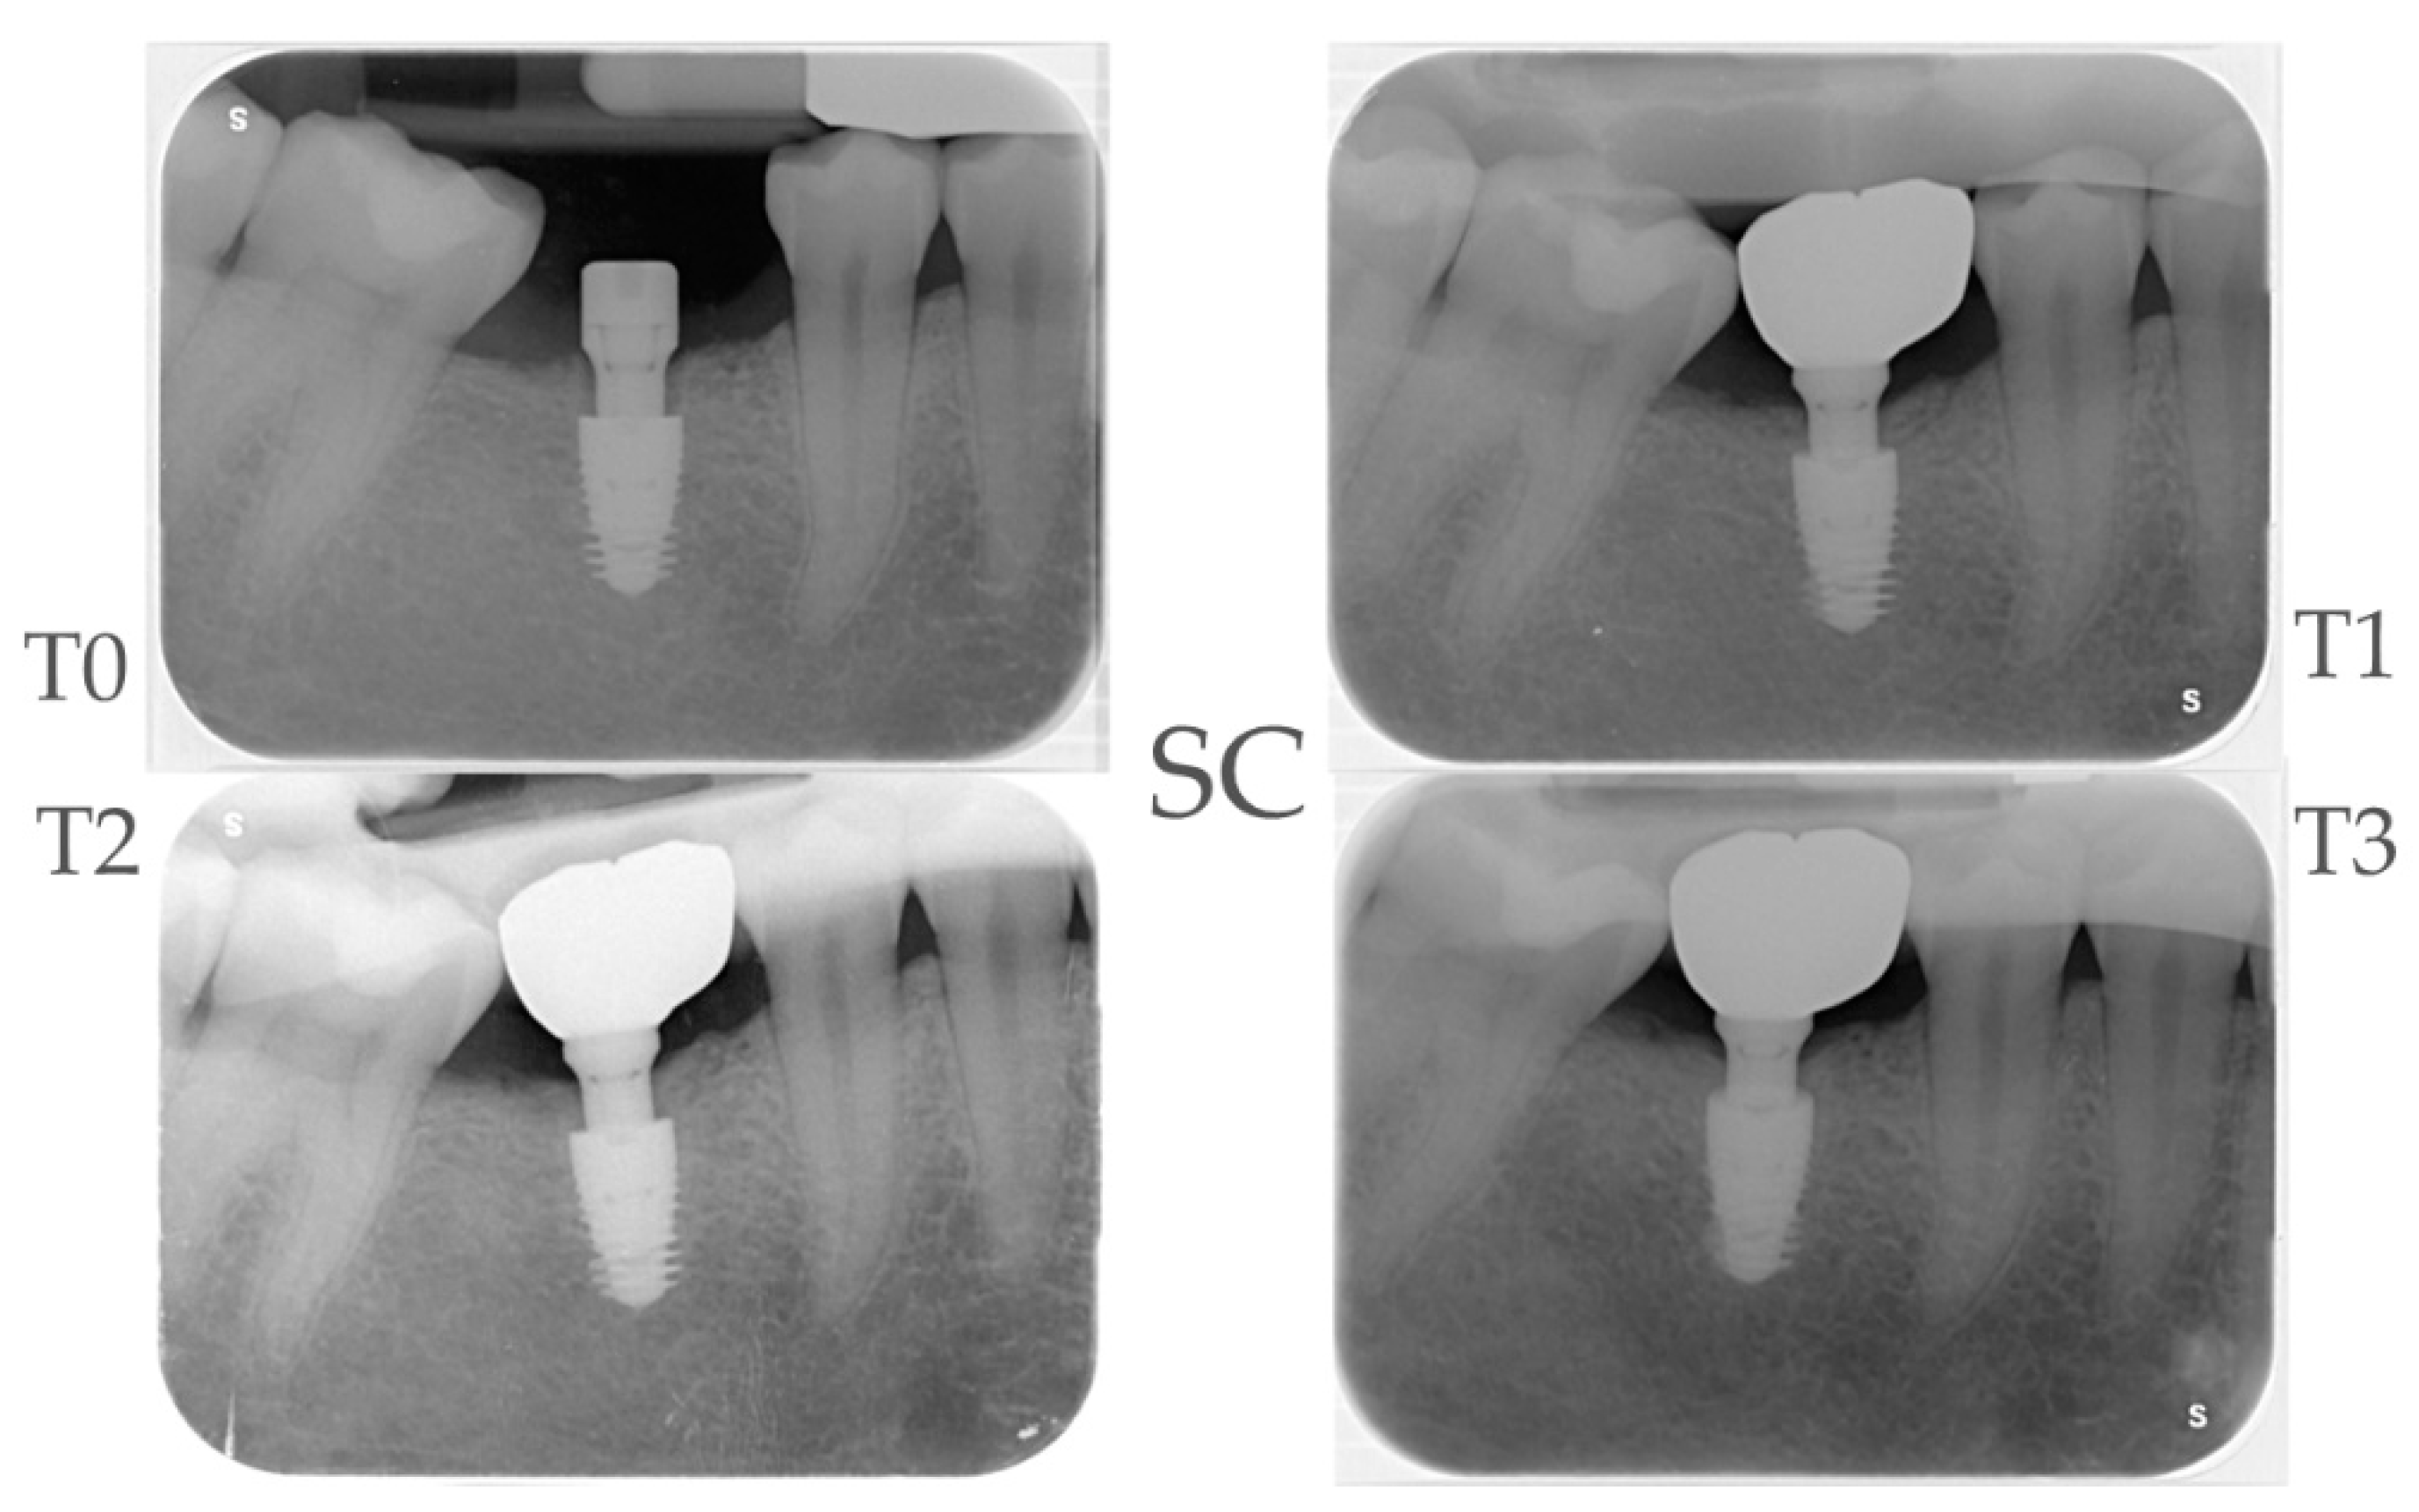

2.4. Radiographic Evaluations

| Time Points | MBM Control Group Δ (CI 95%)** |

P-value | Bone Loss Control Group Δ (CI 95%)** | MBM Test Group Δ (CI 95%)* |

P-value | Bone Loss Test Group Δ (CI 95%)** | MBM Test VS Control Δ (CI 95%) |

P-value |

|---|---|---|---|---|---|---|---|---|

| T1 – T0 | -0.44 (-0.67; -0.21) |

<0.01 | -0.44 (-0.67; -0.21) |

-0.65 (-0.89; -0.42) |

<0.01 | 0 | -0.21 (-0.54; 0.11) |

0.195 |

| T2 – T0 | -0.49 (-0.72; -0.26) |

<0.01 | -0.49 (-0.72; -0.26) |

-0.72 (-0.95; -0.49) |

<0.01 | 0 | -0,23 (-0,55; 0,10) |

0.168 |

| T3 – T0 | -0.52 (-0.75; -0.29) |

<0.01 | -0.52 (-0.75; -0.29) |

-0.60 (-0.83; -0.36) |

<0.01 | 0 | -0.07 (-0.40; 0.25) |

0.657 |